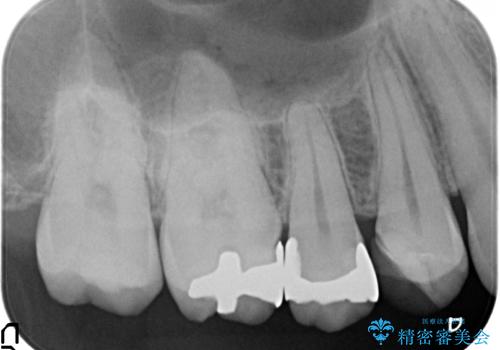

- 歯が痛み、改善を求めて来院されました。

歯の神経の治療(根管治療)が必要であることをご説明し、同時に隣在する銀歯の除去も希望されたので同時に治療を行っていきます.

虫歯治療は小さい場合にはセラミックインレー、大きな場合や痛みが生じている場合は根管治療ののちクラウンによる機能回復が必要となることが多いです。